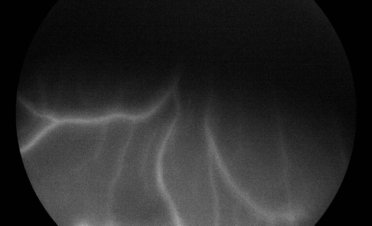

- Angiografía fluoresceínica para evaluar con detalle la vascularización de la retina y coroides.

En la angiografía fluoresceínica se apreció hiperfluorescencia del nervio óptico y en la periferia de la retina. Estas imágenes son compatibles con neuritis óptica y coriorretinitis.